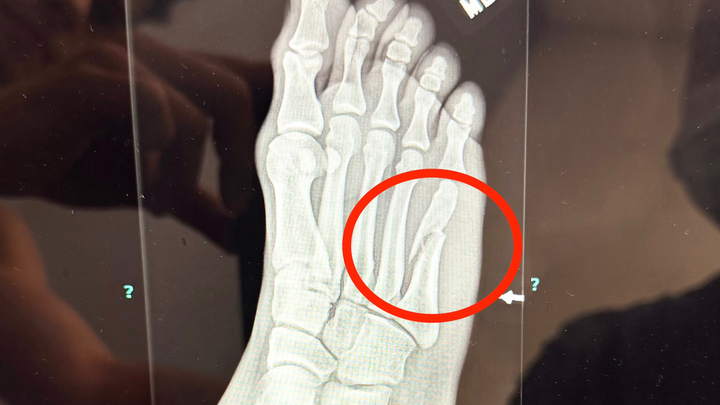

In mid October, during an audition for Romeo and Juliet, I landing awkwardly in petite allegro (doing a pas de bourée, of all steps...) and completely snapped my fifth metatarsal! My orthopedic surgeon is recommending I get surgery, as it will be the most effective treatment with the quickest recovery. If all goes well, I am hoping to be back to dancing by late January!